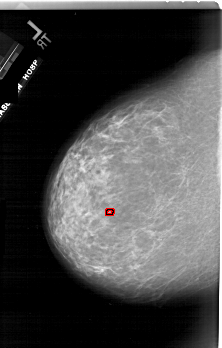

A_1743_1.LEFT_CC

LEFT_CC LINES 6601 PIXELS_PER_LINE 4201 BITS_PER_PIXEL 12 RESOLUTION 43.5 OVERLAY

FILE: A_1743_1.LEFT_CC.OVERLAY

TOTAL_ABNORMALITIES 1

ABNORMALITY 1

LESION_TYPE CALCIFICATION TYPE PLEOMORPHIC DISTRIBUTION CLUSTERED

ASSESSMENT 4

SUBTLETY 2

PATHOLOGY BENIGN

TOTAL_OUTLINES 1